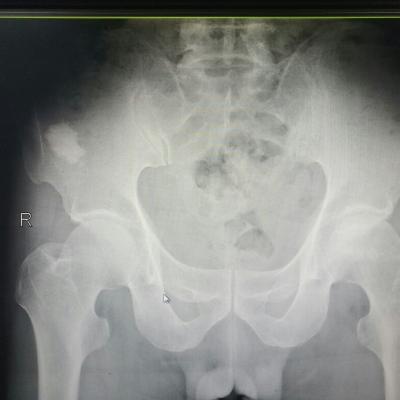

胡桃夹综合征(nutcracker phenomenon)即左肾静脉压迫综合征,又称胡桃夹现象,好发于青春期至40岁左右的男性,儿童发病分布在4~7岁,多发年龄见于13~16岁。 左肾静脉行走在腹主动脉和肠系膜上动脉之间,这两条动脉构成40~60度的夹角,左肾静脉刚好通过此夹角。从解剖上看,右肾静脉径直注入下腔静脉,行程短而直,而左肾静脉需穿过腹主动脉和肠系膜上动脉之间的夹角,跨越腹主动脉前方始能注入下腔静脉,因此左肾静脉远较右肾静脉长。正常时,肠系膜上动脉与腹主动脉之间的夹角被肠系膜、脂肪、淋巴结和腹膜等所充塞,使左肾静脉不致受到压挤。当青春期发育较快、身高迅速增长、脊柱过度伸展、体形急剧变化或肾下垂等情况下,左肾静脉在这个夹角中受到挤压,引起血流变化和相应的临床症状。 胡桃夹现象的主要症状是血尿和蛋白尿,其中无症状肉眼血尿更易发现。血尿的原因是左肾静脉受压致肾静脉高压,左肾静脉扩张所引流的输尿管周围静脉与生殖静脉淤血、与肾集合系统发生异常交通,或部分静脉壁变薄破裂,引起非肾小球性血尿,还会发生睾丸静脉和卵巢静脉淤血而出现肋腹痛,并于立位或行走时加重。另外男性还能发生精索静脉曲张。此外有蛋白尿,不规则月经出血,高血压等。此病的诊断标准为:一侧肾出血;尿红细胞形态为非肾小球性;尿中钙排泄量正常;膀胱镜检查为左侧输尿管口喷血或血性尿;腹部彩超或CT检查可见左肾静脉扩张等。